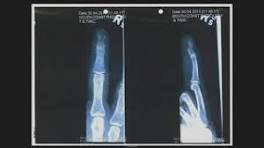

Johnny Depp Trial: Orthopedic surgeon testifies on Depp's finger injury | FOX 5 DC - YouTube Orthopedic surgeon Dr. Richard Gilbert testifies on how he believes Johnny Depp could have injured his finger, saying Amber Heard's rendition of ...

Johnny Depp expert: 'Highly unlikely' Amber Heard story about finger injury is true - YouTube Dr. Richard Gilbert, an orthopedic surgeon hired by Johnny Depp's legal team in his defamation trial against his ex-wife Amber Heard, ...